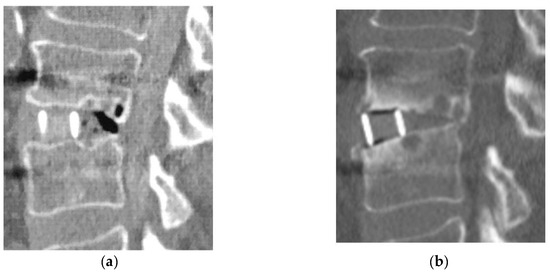

For clinical outcomes, the improvement ratio of the JOA score was 50.9% (−26.3–81.0%) in Group D and 57.9% (0–84.2%) in Group L, with no significant between-group difference. Bone fusion was observed in 11 of 15 patients (73.3%) in Group D and 56 of 62 patients (90.3%) in Group L. All four patients in Group D who did not achieve bone fusion had bone cysts around the cage and a loosening of the screws. One patient in Group D (diabetic nephropathy, Stage 2) (6.7%) had restenosis due to cage subsidence 2 years after LLIF with PPS and underwent additional decompression (Table 3) (Figure 3).

Figure 3.

Reoperation case in Group D. (a): Immediate post-operative CT image; (b): 2-year postoperative CT image.

The reoperation rate for HD patients in the current study was 17.2%, which was significantly higher than that of non-HD patients [17]. In HD patients, Yamada T et al. reported that 8 of 29 patients (27.6%) needed revision surgery after lumbar fusion or decompression surgery [19]. In this study, 1 of 15 patients in Group D required reoperation during the follow-up period. Postoperative restenosis due to cage subsidence was observed in one patient. It was a reoperation case. One of the characteristics of LLIF is that indirect decompression can be obtained [29,30], but, on the other hand, reoperation due to insufficient indirect decompression caused by endplate failure has been noted as an issue with LLIF [31]. Indications for indirect decompression for hemodialysis spondylolisthesis should be carefully selected in light of amyloid deposition and the progression of postoperative destructive bone lesions; in some cases, additional direct decompression may be advisable.